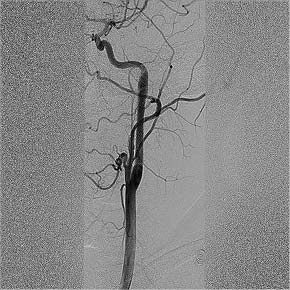

Пациент был доставлен в рентген-операционную, где с использованием правого трансфеморального доступа выполнены диагностическая каротидная ангиография и тотальная цереброангиография. На ангиограммах выявлена окклюзия левой ВСА с визуализацией диссекции в шейном отделе в виде симптома «пламени свечи» (рис. 1).

Рис. 1. Симптом «пламени свечи» в интракраниальном сегменте левой внутренней сонной артерии